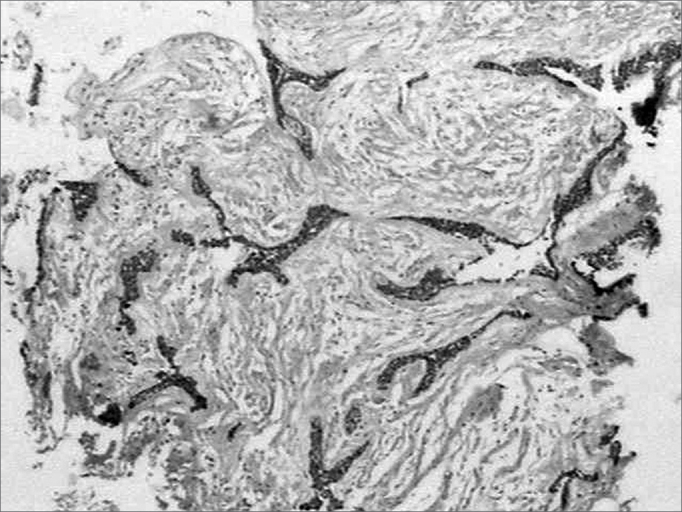

Collagen I

Similar to fibronectin, all along the tumoral stroma of the hybrid lesion in the desmoplastic ameloblastoma, there was an intense immune marking for this ECM protein, in a fibrillar pattern involving the tumoral islets (Figure 4). Sometimes, on the epithelium/mesenchyma interface, we noticed intense linear immune marking, specially on the areas corresponding to the conventional ameloblastoma. Moreover, we noticed lack of type I collagen inside these tumoral cells.

Figure 4.

Strong affinity with type I collagen in a fibrillar pattern on the desmoplastic stroma of the lesion (streptavidine biotin, 40x).